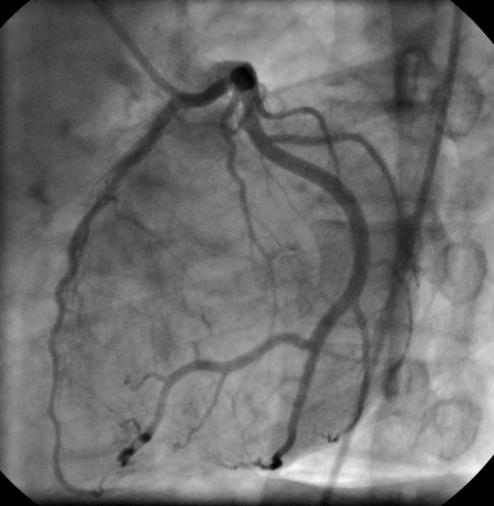

Darstellung der Herzkranzgefäße mittels Koronarangiographie: Bei einer Koronarangiographie (Herzkatheteruntersuchung) wird über eine periphere Arterie ein Katheter eingebracht und über die Aorta bis in die Koronargefäße vorgeschoben. Anschließend wird ein Kontrastmittel appliziert um die Gefäße mittels Röntgendurchleuchtung sichtbar zu machen. © WmCo "Bionerd", Darstellung der Herzkranzgefäße mittels Koronarangiographie: Bei einer Koronarangiographie (Herzkatheteruntersuchung) wird über eine periphere Arterie ein Katheter eingebracht und über die Aorta bis in die Koronargefäße vorgeschoben. Anschließend wird ein Kontrastmittel appliziert um die Gefäße mittels Röntgendurchleuchtung sichtbar zu machen. © WmCo "Bionerd",

Die Koronarangiographie ist eine interventionelle röntgengestützte Untersuchung des Herzens bzw. der Herzkrankgefäße. Dabei wird über eine Arterie (klassisch über die Leistenarterie) ein Katheter eingebracht und bis zum Herz bzw. bis knapp vor das Herz zu den Abgängen der Koronargefäße aus der Aorta vorgeschoben. Anschließend wird ein Kontrastmittel appliziert um den Ventrikel (Ventrikulographie) bzw. die Gefäße (Koronarangiographie) mittels Röntgen sichtbar zu machen.

Bei der Koronarangiographie werden die Herzkranzgefäße auf signifikante Engstellen, welche das Substrat einer koronaren Herzkrankheit, eines akuten Koronarsyndroms bzw. eines Herzinfarktes darstellen, untersucht. Im Rahmen des Vorganges können diese Engstellen auch gleich behandelt werden (PCI , Percutaneous Coronary Intervention; PTCA , Perkutaneous Transluminal Coronary Angioplasty). Als Optionen stehen die Dehnung mittels eines Ballons und/oder die Einbringung eines Stents in das betroffene Gefäß zur Wahl. Ein Stent ist vom Prinzip aufgebaut wie ein sich selbst aufspannendes, schlauchförmiges Metallgitter, welches in das Gefäß eingebracht wird und dieses an der betreffenden Stelle aufdehnt. Es gibt unbeschichtete (BMS, Bare Metal Stent) und beschichtete (DES, Drug Eluting Stent) Stents.